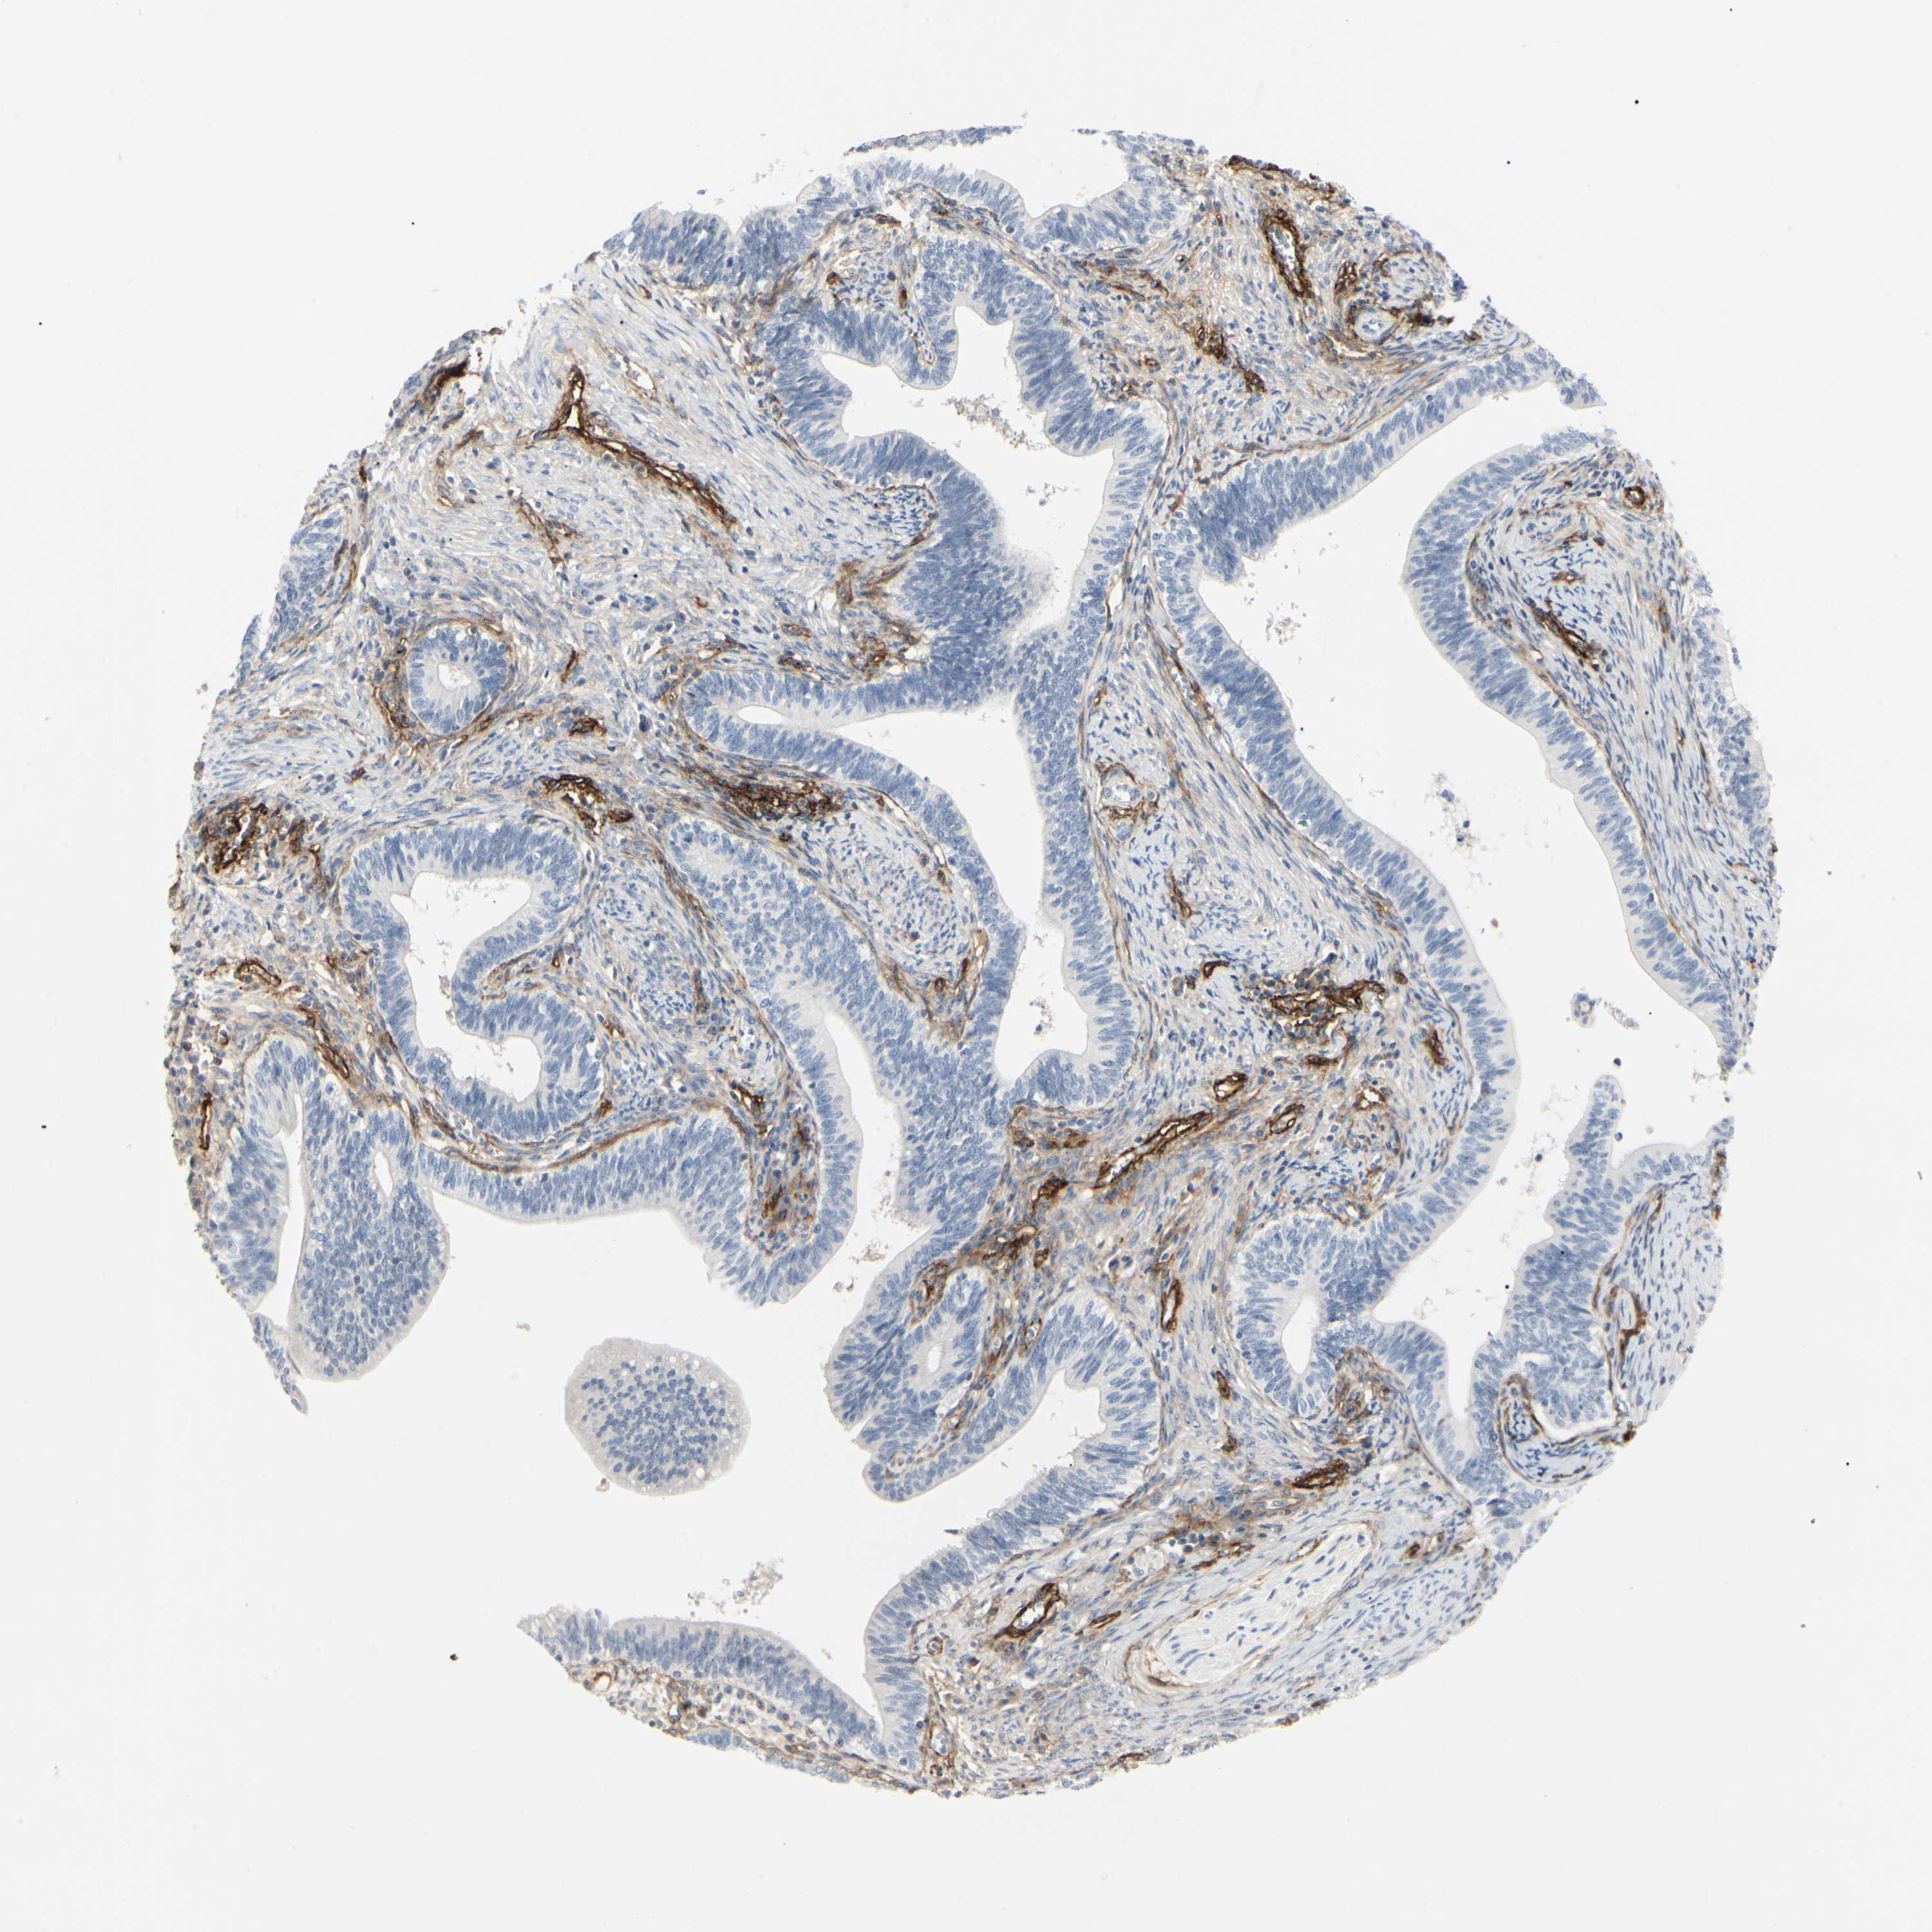

CERVICAL CANCER - Protein expressioni

A mouse-over function shows sample information and annotation data. Click on an image to view it in a full screen mode. Samples can be filtered based on level of antibody staining by selecting one or several of the following categories: high, medium, low and not detected. The assay and annotation is described here.

Note that samples used for immunohistochemistry by the Human Protein Atlas do not correspond to samples in the TCGA dataset.

Antibody stainingi

Antibody staining in the annotated cell types in the current human tissue is reported as not detected, low, medium, or high, based on conventional immunohistochemistry profiling in selected tissues. This score is based on the combination of the staining intensity and fraction of stained cells.

Each image is clickable and will lead to virtual microscopy that enables deeper exploration of all samples and also displays staining intensity scores, fraction scores and subcellular localization as well as patient and tissue information for each sample.

Antibody HPA008121

Antibody CAB032489

Squamous cell carcinoma, NOS

Adenocarcinoma, NOS